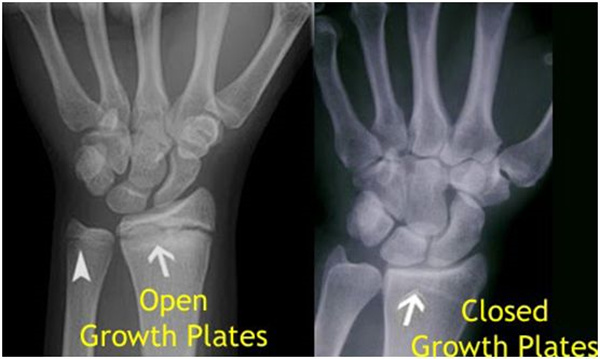

我們都知道,人體的高矮是由骨骼的生長(zhǎng)發(fā)育決定的,特別是下肢長(zhǎng)骨。長(zhǎng)骨呈長(zhǎng)管狀,在長(zhǎng)骨的兩端有一種專管骨骼生長(zhǎng)的骺軟骨,它與干骺端之間有一盤狀軟骨結(jié)構(gòu)稱為骺板(線),在幼兒的X光片上表現(xiàn)為一條較寬的透光帶。(見(jiàn)下圖)

未成年時(shí)隨著年齡的增加骺軟骨端不斷骨化,骨骼就不斷增長(zhǎng)。當(dāng)骨骺線完全閉合時(shí)骨骼就停止生長(zhǎng),個(gè)子也就不再增長(zhǎng)了。一般骨骺端完全閉合的年齡是18~20歲左右。

讀到這里,可能很多人又會(huì)有這樣一個(gè)疑問(wèn):骨骺線會(huì)不會(huì)提前閉合呢?

答案是會(huì)的。

骨骺線提前閉合最多見(jiàn)的情況是性早熟,而這也是很多醫(yī)生專家建議孩子進(jìn)行骨齡測(cè)量的原因之一。另外,在兒童時(shí)期大量補(bǔ)鈣也會(huì)使骨骺端提前過(guò)早閉合。

青少年一般什么時(shí)候骨骺閉合?

一般女孩是在16歲,男孩是在18歲。

一般來(lái)說(shuō),女孩的骨齡超過(guò)14歲,男孩的骨齡超過(guò)16歲,這時(shí)其骨骺線已接近閉合,基本沒(méi)有長(zhǎng)高的機(jī)會(huì)了。